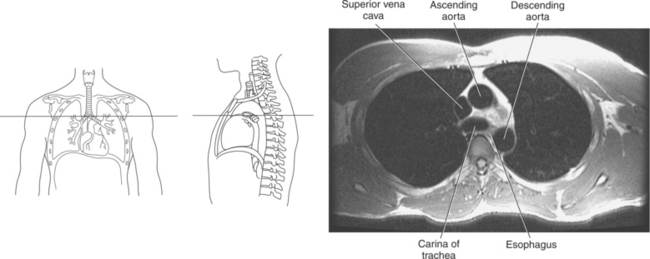

Blood travels to and from the heart through the great vessels, which include the aorta, pulmonary arteries and veins, and superior and inferior venae cavae (Figures 6.54 and 6.55). The aorta is the largest artery of the body and can be divided into the ascending aorta, aortic arch, and descending aorta. The ascending aorta begins at the base of the left ventricle at the level of the sternal angle, then curves superiorly and posteriorly as the aortic arch over the root of the left lung. The top of the aortic arch is approximately at T3 (Figures 6.56 and 6.57). The arch continues as the descending aorta posterior to the left bronchus and pulmonary trunk, on the left side of the vertebral body of T4 (Figures 6.58 and 6.59). The descending aorta passes slightly anterior and to the left of the vertebral column as it descends through the thoracic and abdominal cavities (Figure 6.60). While in the thoracic cavity, the descending aorta is commonly called the thoracic aorta, and while in the abdominal cavity, it is called the abdominal aorta. The pulmonary trunk is the origin of the right and left pulmonary arteries and lies entirely within the pericardial sac. It arises from the right ventricle and ascends in front of the ascending aorta, courses posteriorly and to the left, where it bifurcates at the level of the sternal angle (T4) into the right and left pulmonary arteries (Figures 6.61 through 6.63). The pulmonary trunk is attached to the aortic arch by a fibrous cord called the ligamentum arteriosum, the remnant of an important fetal blood vessel (ductus arteriosus) that links the pulmonary and systemic circuits during fetal development (Figures 6.54 and 6.61). The right pulmonary artery courses laterally, posterior to the ascending aorta and superior vena cava, and anterior to the esophagus and right mainstem bronchus, to the hilum of the right lung. At the root of the right lung, the right pulmonary artery divides into two branches, with the lower branch supplying the middle and inferior lobes and the upper branch supplying the superior lobe (Figures 6.61 through 6.64). The left pulmonary artery, shorter and smaller than the right, is also the most superior of the pulmonary vessels. It travels horizontally, arching over the left mainstem bronchus, and enters the hilum of the left lung just superior to the left mainstem bronchus (Figures 6.61 through 6.64). Within the lungs, each pulmonary artery descends posterolateral to the main bronchus and divides into lobar and segmental arteries, continuing to branch out and to follow along with the smallest divisions of the bronchial tree (Figures 6.61 and 6.64). Located inferior to the pulmonary arteries are the four pulmonary veins, two each (superior and inferior) extending from each lung to enter the left atrium (Figures 6.54, 6.55, 6.61, and 6.64 through 6.68). They commence in a capillary network along the walls of the alveoli, where they are continuous with the capillaries of the pulmonary arteries. The venous capillaries merge to form small vessels that unite successively to eventually form a single trunk for each lobe: three for the right and two for the left lung. Frequently the trunk from the middle lobe of the right lung unites with the trunk from the upper lobe, forming just two trunks on the right side prior to entering the left atrium. The right superior pulmonary vein collects blood from the upper lobe segments of the right lung and passes anterior and inferior to the right pulmonary artery, behind the superior vena cava. The right inferior pulmonary vein receives blood from the right lower lobes of the lung and crosses behind the right atrium to the left atrium (Figures 6.61 and 6.69 through 6.71). The left superior pulmonary vein receives blood from the left upper lobe of the left lung and courses anterior and inferior to the left main bronchus as it enters the left atrium. The left inferior pulmonary vein drains the inferior lobe of the left lung and passes toward the left atrium anterior to the bronchi (Figures 6.61 and 6.72 through 6.74). The pulmonary veins course more horizontally than the pulmonary arteries and are ultimately oriented toward the left atrium. At the root of the lungs, the pulmonary veins are anterior to the pulmonary arteries, which are anterior to the bronchus. While within the lungs, the branches of the pulmonary arteries are anterior to the bronchi, which are anterior to the pulmonary veins. The superior and inferior venae cavae are the largest veins of the body. The superior vena cava is formed by the junction of the brachiocephalic veins, posterior to the right first costal cartilage, and carries blood from the thorax, upper limbs, head, and neck (Figure 6.24). As it travels inferiorly, it is located posterior and lateral to the ascending aorta before entering the upper portion of the right atrium (Figures 6.54 through 6.59). The inferior vena cava is formed by the junction of the common iliac veins in the pelvis and ascends the abdomen to the right of the abdominal aorta and anterior to the vertebral column. It passes through the caval hiatus of the diaphragm and almost immediately enters the inferior portion of the right atrium (Figures 6.75 and 6.76).

Figure 6.59 Axial CT scan of chest with ascending and descending aorta.

Key: SVC, Superior vena cava; asa, ascending aorta; da, descending aorta; ca, carina;